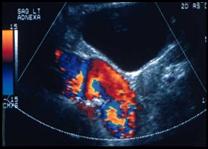

Transverse                          Sagittal